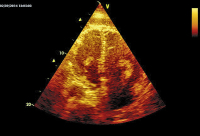

Abbildung 1: Echoreiche Massen in der linken und der (mäßig dilatierten) rechten Kammer.